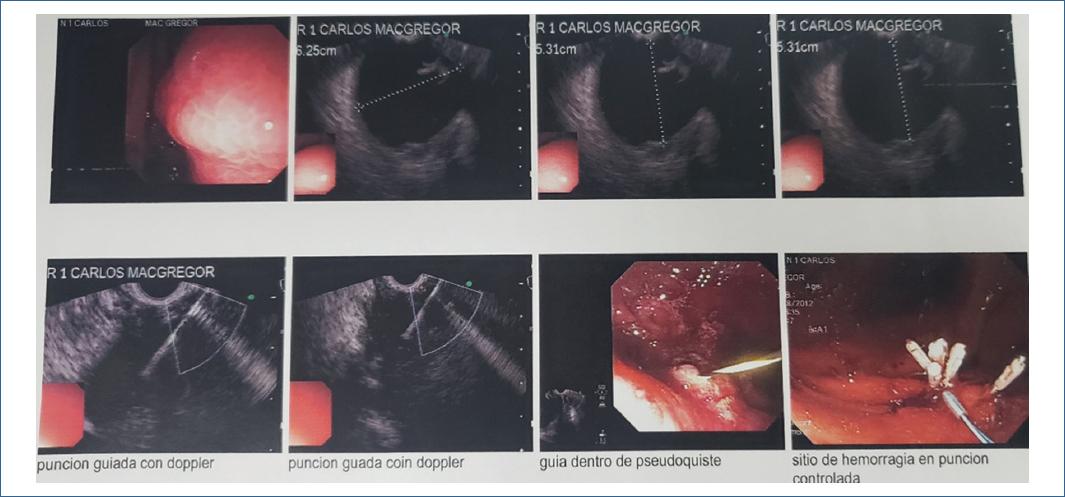

Técnica de drenaje por ultrasonido endoscópico

La técnica de drenaje endoscópico no está estandarizada y el tipo de endoscopio utilizado puede variar según la disponibilidad y las necesidades técnicas. En aquellos casos en que la compresión sea evidente por visualización directa, se puede realizar el drenaje completo con un duodenoscopio y apoyo por fluoroscopia. Sin embargo, se recomienda realizar el drenaje guiado por ecoendoscopia ya que permite identificar la presencia de vasos sanguíneos y medir la distancia entre la luz gastroduodenal y la cavidad del pseudoquiste. Una distancia mayor de 1cm se asocia a mayor riesgo de perforación. Los ecoendoscopios sectoriales con canal terapéutico permiten realizar todo el procedimiento y son cada vez más los autores que recomiendan siempre su uso en el abordaje inicial. Si no se dispone de ecoendoscopio terapéutico, se puede identificar el sitio óptimo de punción mediante ecoendoscopia y a continuación realizar la punción, dilatación y drenaje con un duodenoscopio con apoyo de la fluoroscopia. En la mayoría de nuestros pacientes no fue requerido el uso del fluoroscopio.

Punción del pseudoquiste: Bajo control ecoendoscópico y con apoyo de fluoroscopia, se realiza la punción en el punto seleccionado en la pared del estómago o del duodeno, con una aguja de 18 o 19 G hasta penetrar en la cavidad del pseudoquiste. La aspiración del líquido del seudoquiste y la inyección de contraste confirma la correcta posición de la aguja. El abordaje perpendicular de la aguja con respecto al pseudoquiste permite la instrumentación con mayor facilidad. Otras formas descritas para realizar esta comunicación entre la cavidad quística y la luz gastrointestinal son el uso directo del needle-knife, o a través de electrocauterio usando la punta de un asa de polipectomía.o con precorte como en uno de nuestro casos.

Inserción de la guía: La inserción de la guía hidrofílica angulada (0,035-inch × 450cm) dentro del seudoquiste asegura la posición y permite el paso de instrumentos accesorios dentro de la cavidad. La guía es avanzada bajo control radiológico, hasta lograr varios loops dentro de la cavidad del pseudoquiste y evitar su salida; paso que omitimos en la mayoría de nuestros casos.